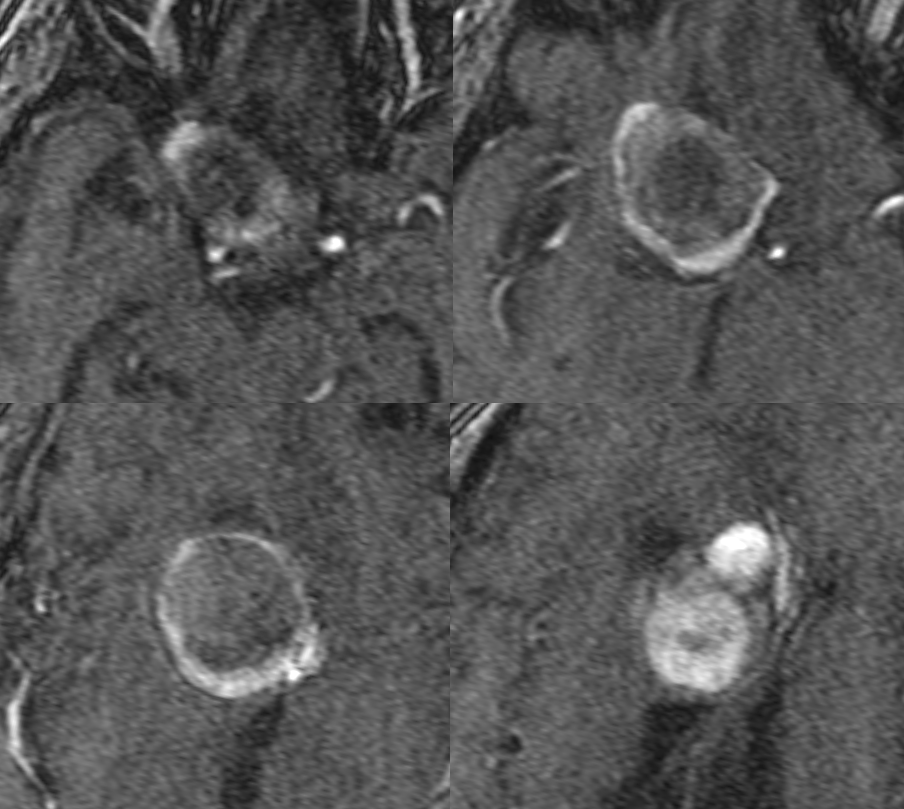

A — vision loss

MRI – pre-T1 (top), post (middle), FLAIR, T2, Diffusion (bottom)

MRA